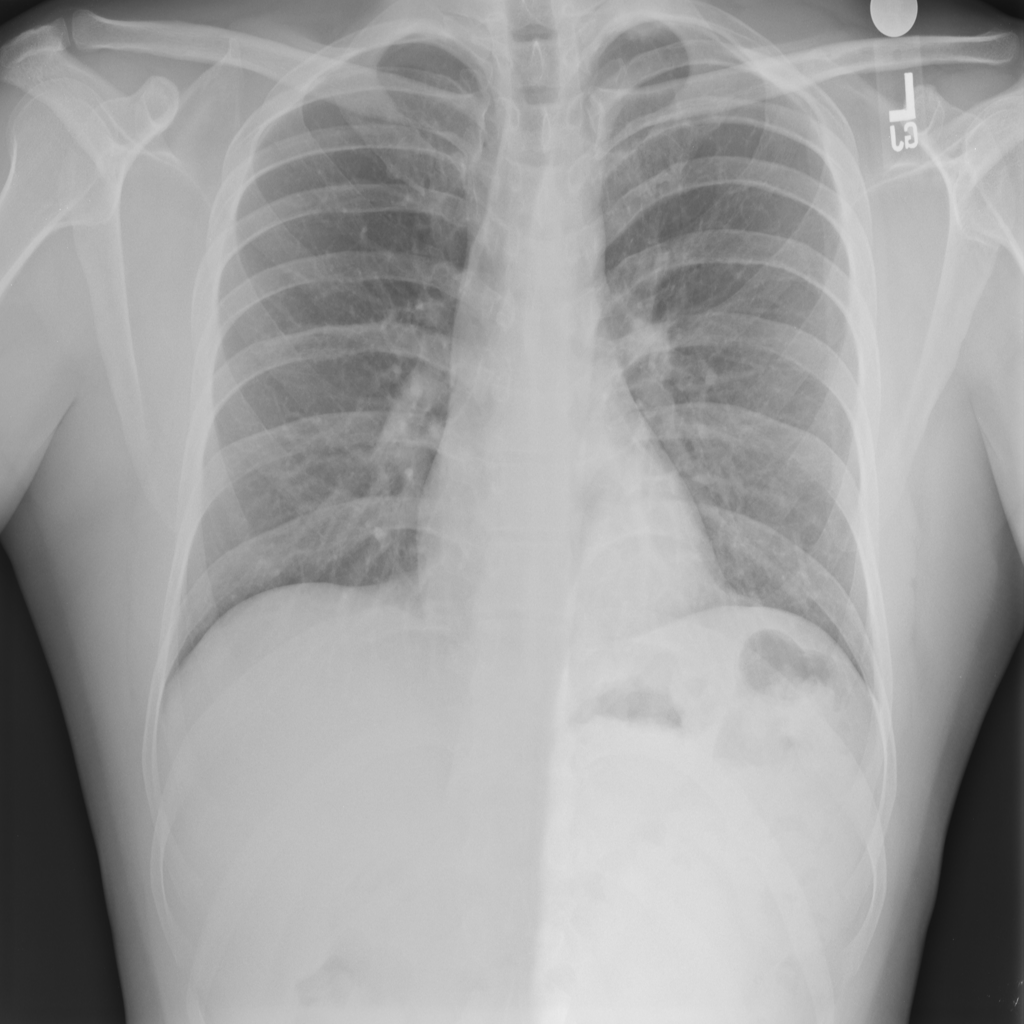

PAT-C77C · IMG-003Fibrosis

PAT-C77C · IMG-003

PA